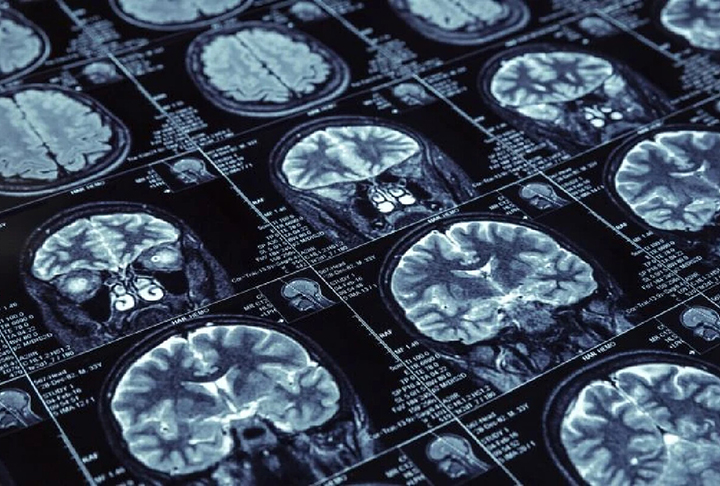

Primeira paciente vítima de Alzheimer ficou na história